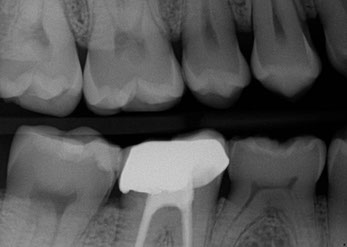

HD Digital X-ray Root Canal & Crown